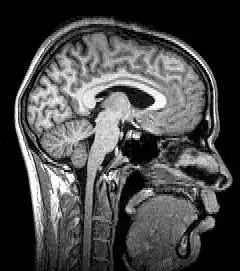

La tomografía es el proceso de obtención de imágenes (cada una de ellas llamada tomograma) por secciones mediante el uso del tomógrafo. Este método se usa en medicina, arqueología, biología, geofísica, oceanografía, ciencia de los materiales y otras ciencias. En la mayoría de los casos se basa en un procedimiento matemático llamado reconstrucción tomográfica. Hay muchos tipos diferentes de tomografía, tal y como se listan posteriormente (nótese que la palabra griega tomos conlleva el significado de ‘cortar’, ‘dividir’ o ‘seccionar’). Una tomografía de varias secciones de un cuerpo es conocida como politomografía.

Las más modernas variaciones de la tomografía involucran la proyección de datos provenientes de múltiples direcciones y el envío de estos datos para la creación de una reconstrucción tomográfica a partir de un algoritmo de software procesado por ordenador. Los diferentes tipos de adquisición de las señales pueden ser utilizados en algoritmos de cálculo similares, a fin de crear una imagen tomográfica. Actualmente, las tomografías se obtienen utilizando diferentes fenómenos físicos, tales como rayos X, rayos gamma, aniquilación de electrones y positrones - reacción, resonancia magnética nuclear, Ultrasonido, iones y electrones. Estos se denominan: TC, SPECT, PET, MRI, ultrasonografía, 3D TEM y átomo sonda, respectivamente.

- imagen por resonancia magnética (MRI), conocida formalmente como tomografía de resonancia magnética (MRT) o tomografía de resonancia magnética nuclear